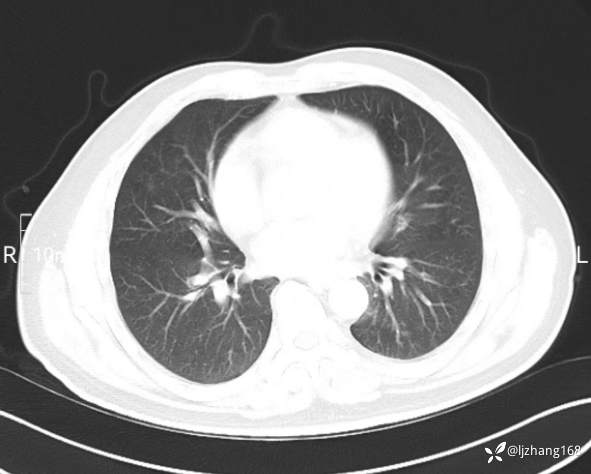

辅助检查:糖化血红蛋白12.3%。肺炎支原体IgG、IgM、呼吸道合胞病毒均未见明显异常。胸部CT:右肺上叶阻塞性肺炎。